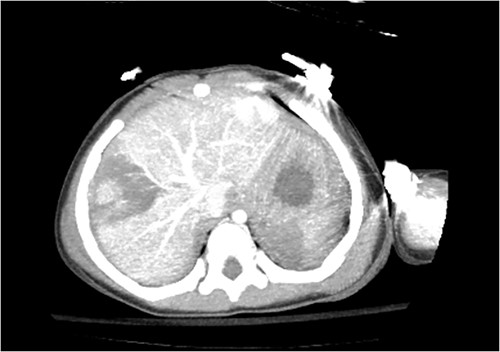

Computed tomography (CT) of the head and spine showed no other injuries. CT chest, abdomen, and pelvis showed a femoral neck fracture, grade IV liver injury, grade II splenic injury, and a fracture of the left iliac wing (Figs 1 and 2), along with a left sided bladder hematoma secondary to a pubic ramus fracture (Fig. 3). Interventional radiology was consulted to evaluate the liver and splenic injuries.